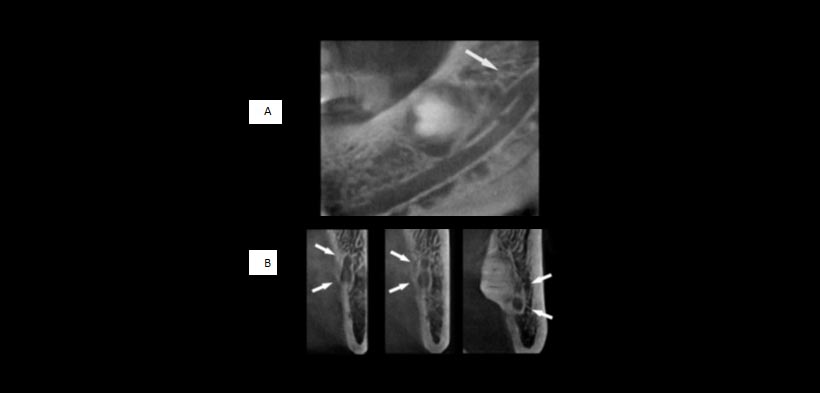

Fig 2. (A y B) imágenes de CBCT de la mandíbula derecha (varón, 52 años). (C) imagen de la radiografía panorámica. Las imágenes de la tomografía (A y B) revelan claramente un corto canal mandibular bífido que se extiende a la tercera molar inferior (Tipo II, flechas), que no se ve en (c) (flecha)